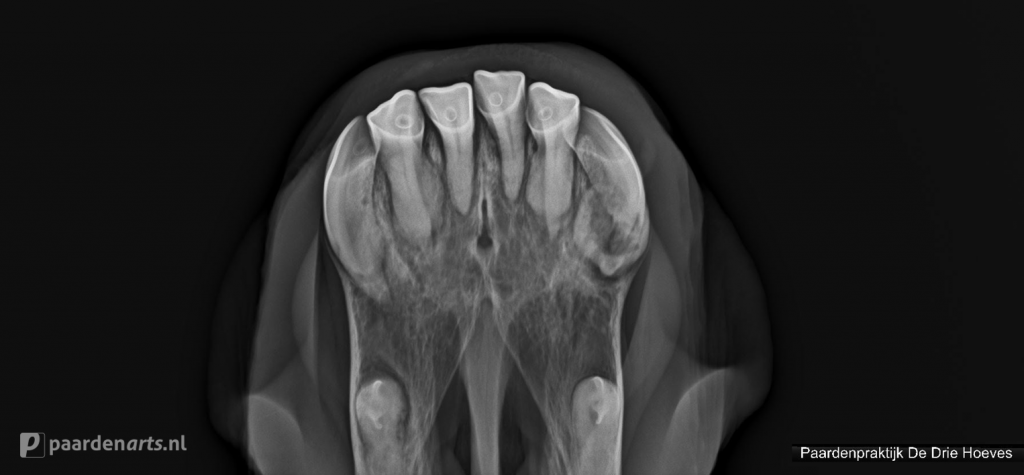

Gebitsproblemen

In geval van gebitsproblemen kan het ook nuttig zijn om röntgenopnames te maken. Op deze manier kan er namelijk gekeken worden of er sprake is van EOTRH, kieswortelontsteking, diastases etc.